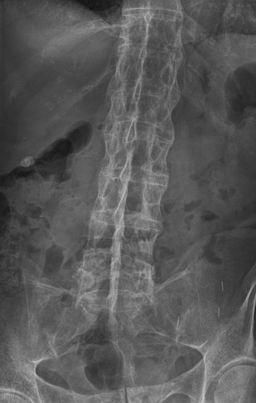

Les corps vertébraux peuvent devenir "carrés". À un stade plus avancé, des ponts osseux (syndesmophytes) se forment entre les vertèbres adjacentes, il y a ossification des ligaments vertébraux et, à un stade avancé de la maladie, il peut y avoir fusion complète de la colonne vertébrale (colonne de bambou).

Dos en bambou

Par Stevenfruitsmaak, via Wikimedia Commons